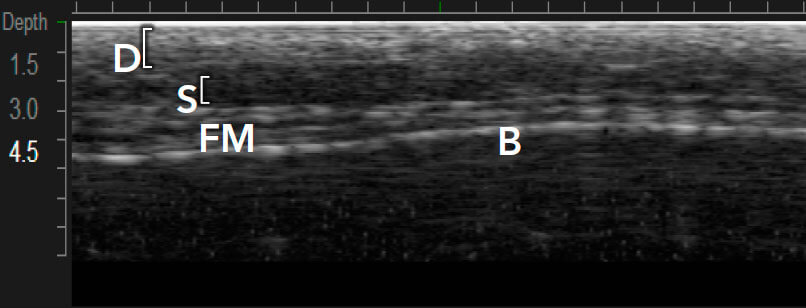

Приклади варіантів структури шкіри між індивідуальними пацієнтами 1,12

Візуалізація в реальному часі є основою Ultherapy®

Ultherapy® доставляє енергію на три глибини (1,5, 3,0 та 4,5 мм) 1,7

MFU-V дає змогу лікарям точно бачити і враховувати всі анатомічні особливості в індивідуальному плані лікування, який буде ефективним.1